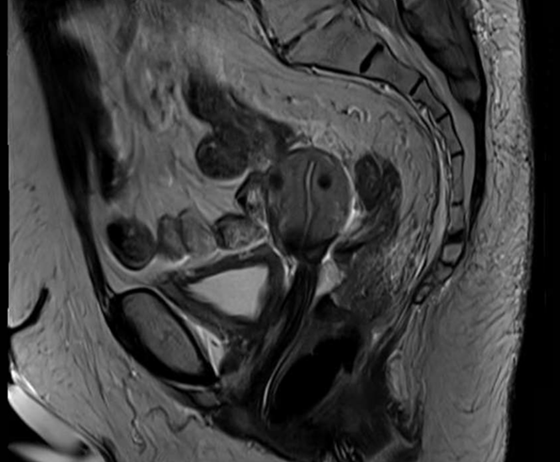

Figure 1 and figure 2 illustrate the typical interfraction movement as seen on the MRI scan. Figure 3 and figure 4 demonstrate the daily changes of the patient’s internal anatomy whilst figure 5 and figure 6 show the adaptive radiotherapy plan.

Fig 1: Internal anatomy during the planning MRI

Fig 2: Internal anatomy during first fraction of treatment

Fig 3: Changes in internal anatomy demonstrated by a smaller rectum on day 3 compared to the planning scan

Fig 4: Changes in internal anatomy demonstrated by a different rectum size on day 4